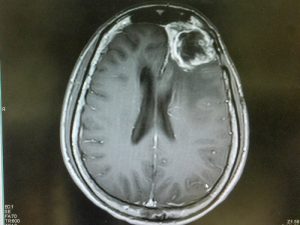

Combined Approach to Glioblastoma Treatment